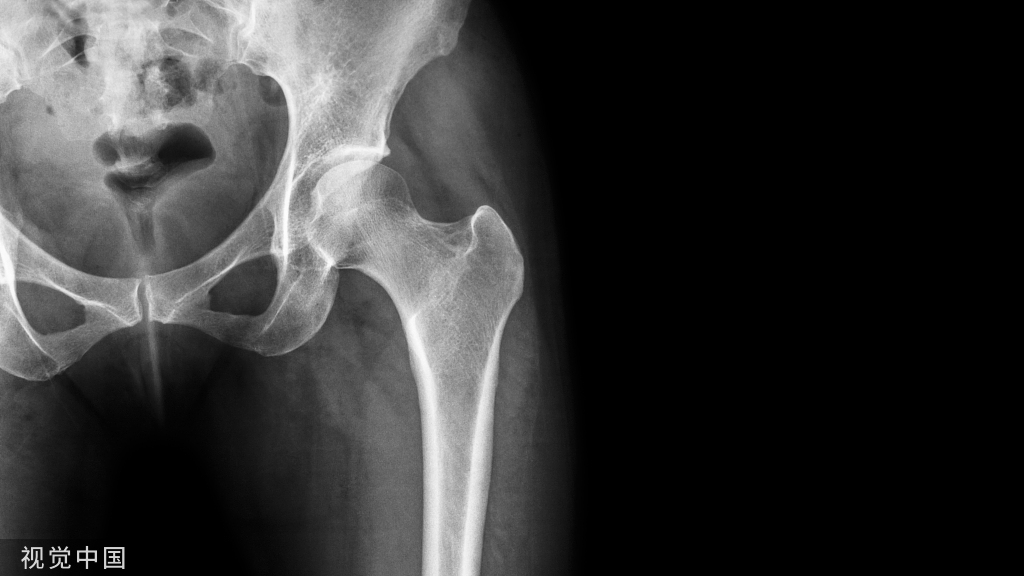

X 线影像学评估是正确诊断的基础,可有效指导临床治疗。

跟骨骨折的 X 线评估主要包括对侧位片和轴位片,Broden位片的测量。